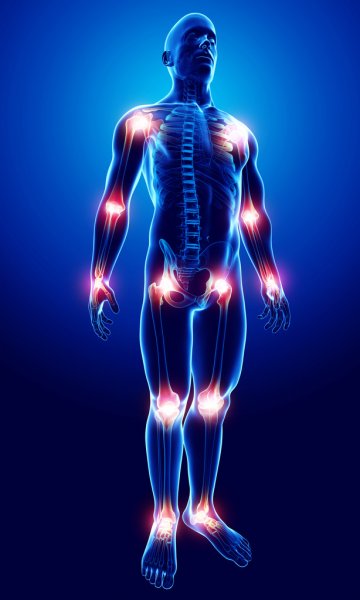

Где может заболеть?

- Плечевой сустав. Боль дает о себе знать, если вы поднимаете или поворачиваете руку, прикладываете физическое усилие.

- Локтевой сустав. Ощущается при сгибании и разгибании, повороте рукой, когда поднимаете тяжести.

- Суставы кистей рук. Неприятные ощущения могут быть при сжимании и разжимании пальцев, попытке взять и удержать что-то в руке, при точечных движениях пальцев - при работе на клавиатуре, например.

- Тазобедренные суставы. Боль может быть как при ходьбе, так и при неподвижном состоянии – когда вы сидите или лежите.

- Коленные суставы. Если у вас на пути лестница – то она может стать серьезным препятствием при боли в колене. Прыгать и забираться на стул с болью в коленном суставе тоже не получится.

- Голеностопный сустав. Даже неторопливая ходьба не принесет вам удовольствие, если даст о себе знать голеностопный сустав.